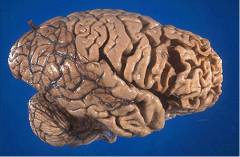

В основе развития деменции лежит гибель клеток головного мозга. Ее причины могут быть различными.

При болезни Альцгеймера происходит гибель нейронов, в головном мозге уменьшается количество нервных связей. Уменьшается объем головного мозга.